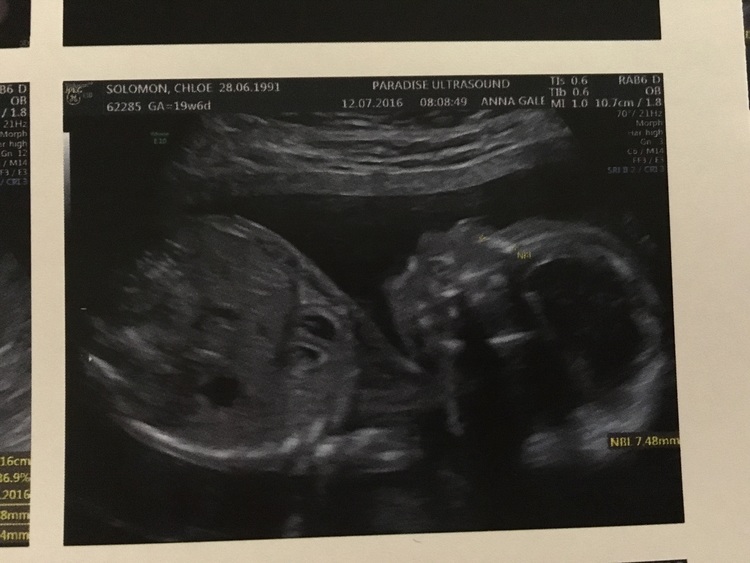

I’m going to be a big brother! July 19, 2016 Author: lancensolomon Woweee, in November i’m going to be a big brother. My little brother, Theodore Rex will be joining my sister and I. I cannot wait to play with him and show him all the cool things in the world 0 0 0 Share this:Click to share on Twitter (Opens in new window)Click to share on Facebook (Opens in new window)Like this:Like Loading...